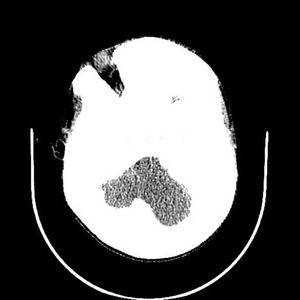

Case History: A 28-year-old man presented with history of pulsing noise in the head and progressive right hemiparesis.